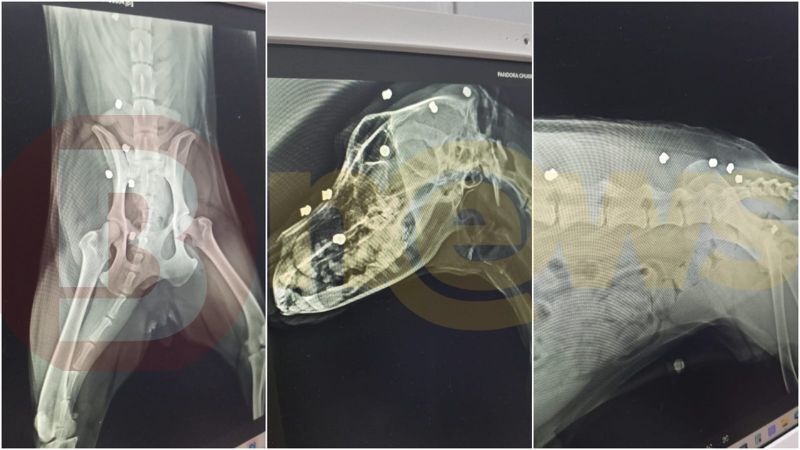

A Polícia Civil foi acionada, na quinta-feira (23), após um morador de um condomínio de luxo na cidade de Lauro de Freitas atirar 17 vezes com uma espingarda contra o cachorro do seu vizinho. A ação teria acontecido após uma desavença entre os inquilinos. O animal sobreviveu.

O morador que efetuou os disparos foi identificado como Marcones. Segundo informações do Bnews, em contato com vizinhos que presenciaram o episódio, o cão teria saído da sua residência e ido para a casa do acusado. Outras fontes dizem que os disparos começaram sem um motivo específico.

Um boletim de ocorrência foi feito pelo tutor do cachorro. A Polícia Civil investiga o caso.